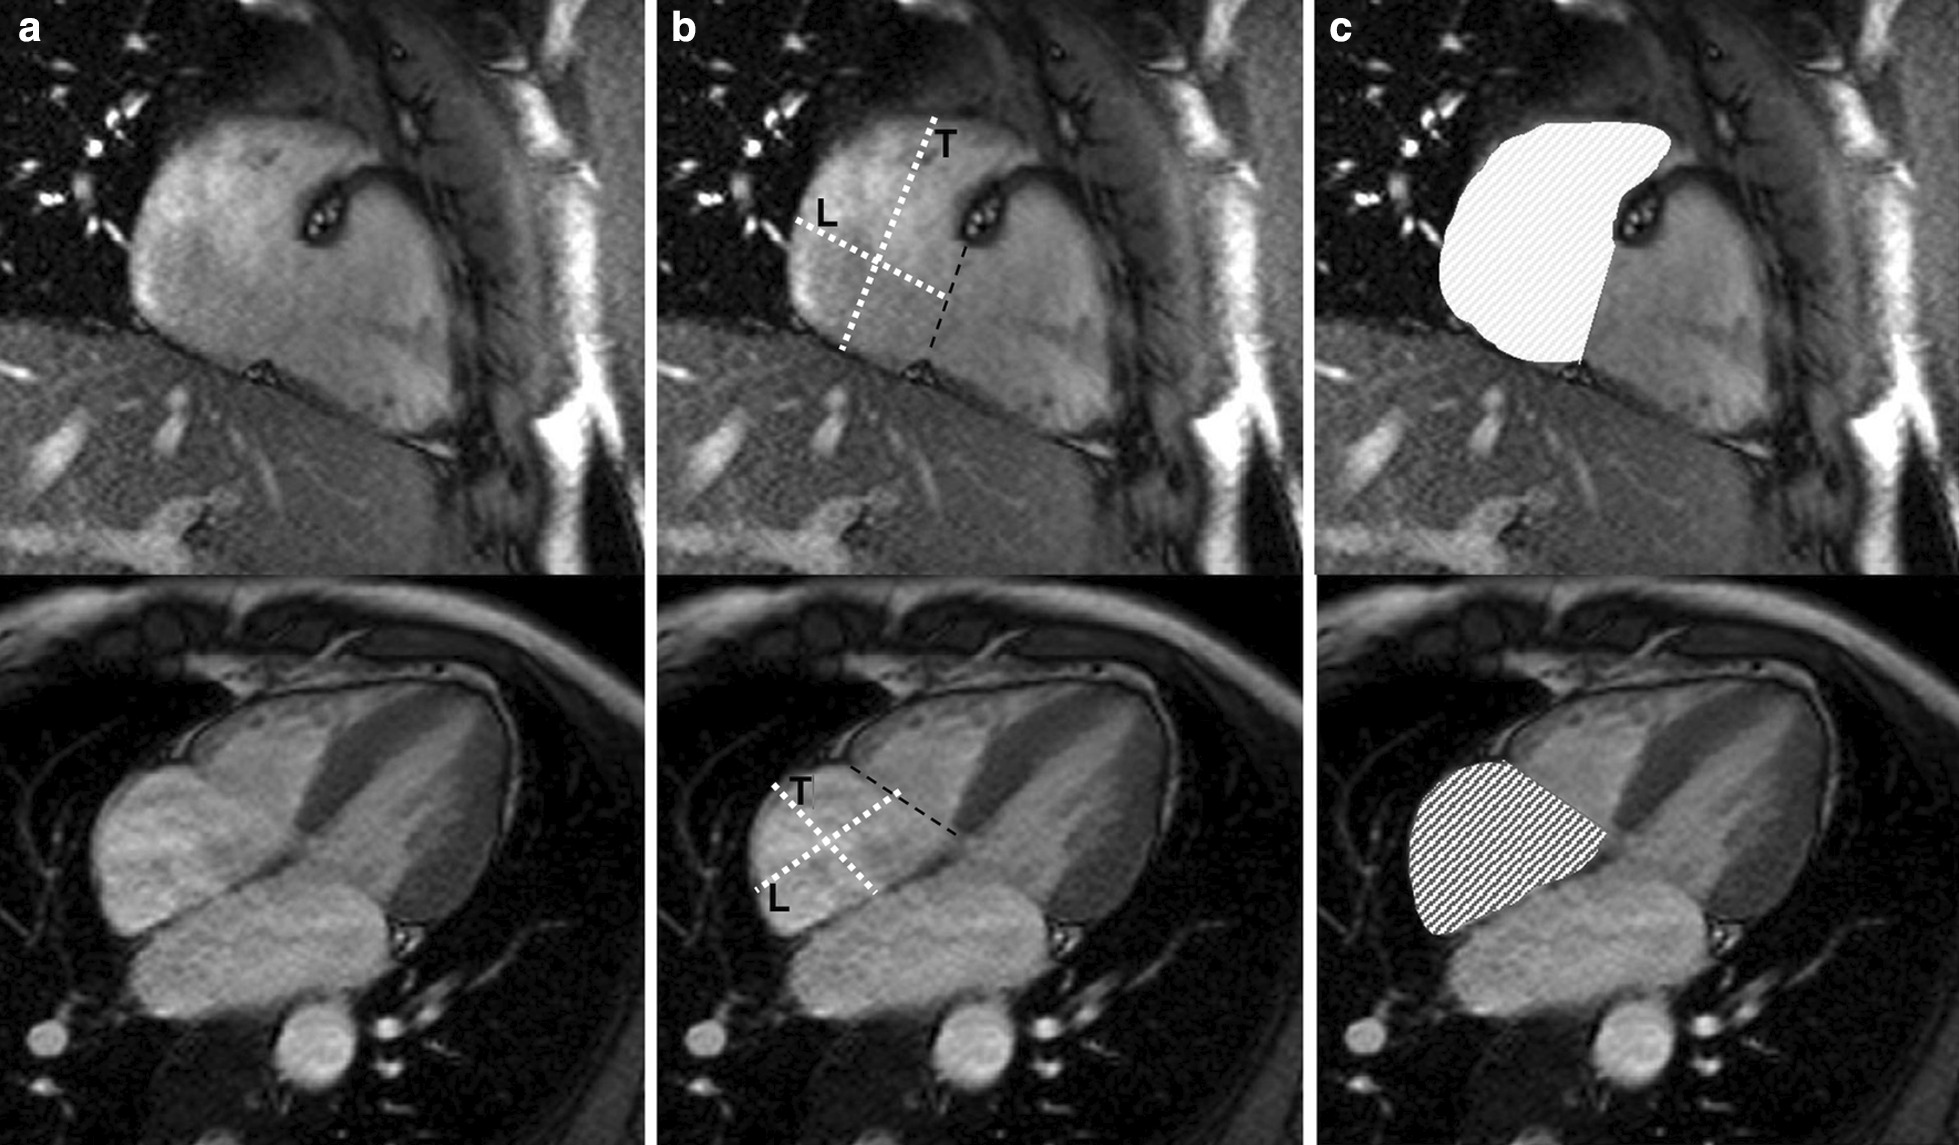

There is no consensus in the literature regarding acquisition and measurement method for the right atrium (RA). Published methods for RA volume include the modified Simpson’s method, the biplane area-length method and 3D-modeling [23, 24, 37]. For Simpson’s method and 3D modeling, a stack of cine bSSFP images in the SAx view are analyzed. For the biplane area-length method, a 4-chamber view and a RV 2-chamber view are utilized [33] (Fig. 4).

Fig. 4.

Measurement of right atrial (RA) parameters according to [37]. Areas and diameters were measured in atrial diastole (maximal size of the left atrium) on the 2-chamber (top row) and 4-chamber (bottom row) views. In B), longitudinal diameter (L) is obtained from the posterior wall of the RA to the center of the tricuspid plane, and transverse diameter (T) is obtained perpendicular to the longitudinal diameter, at the mid level of the RA. C shows measurements of the area for both views including the RA appendage